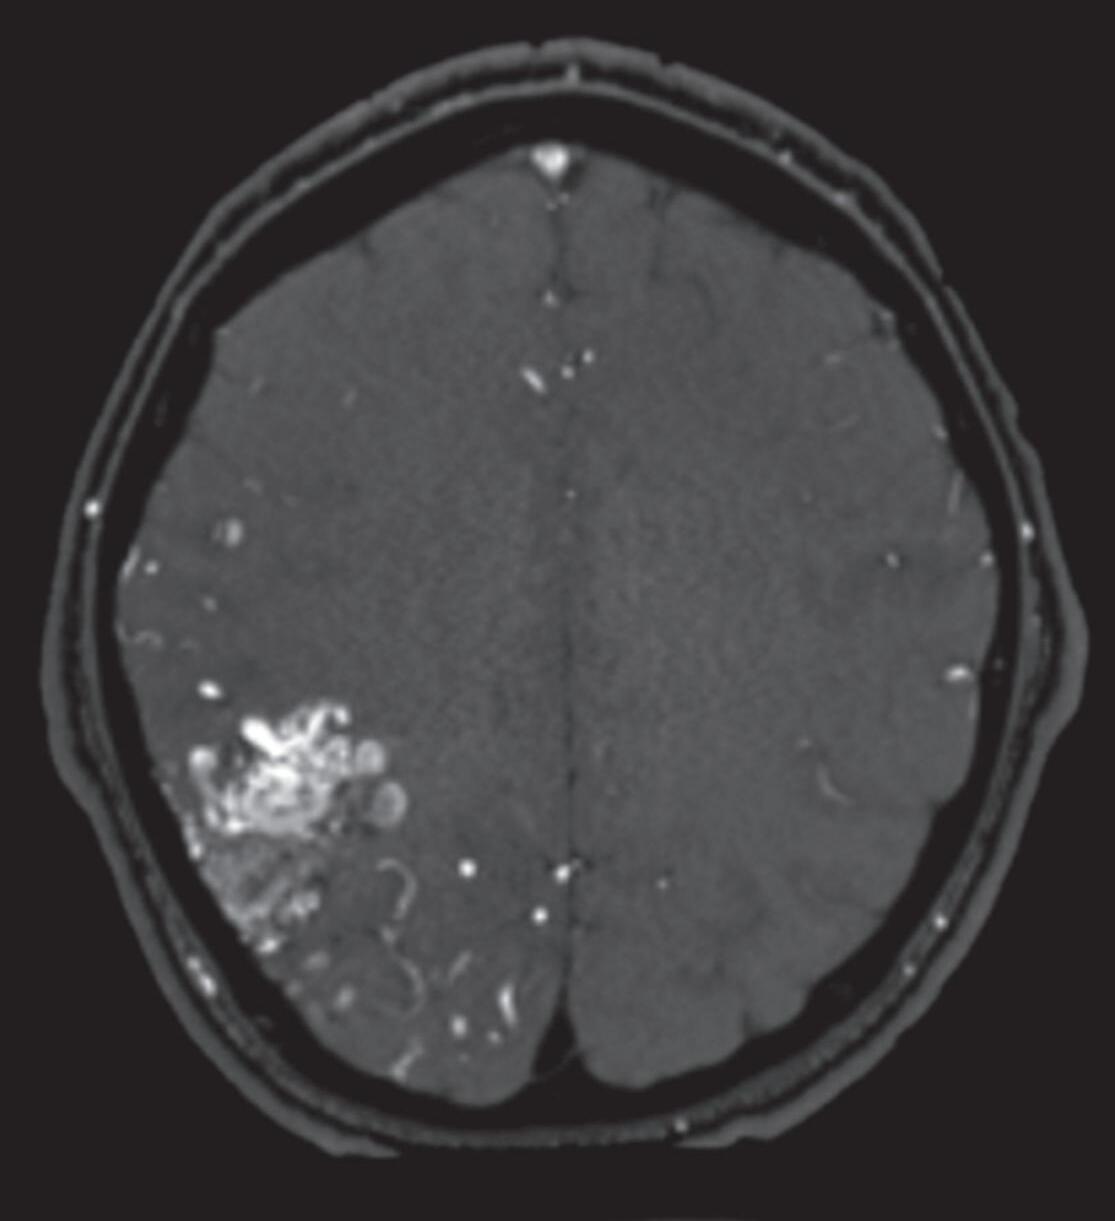

Fig. 1-8. (a-c) RNM T1 com contraste, cortes sagital (a), coronal (b) e axial (c) demonstrando MAV não rota com nidus localizado no lobo occipital à esquerda (setas longas). (d) Arteriografia digital cerebral com injeção de contraste via carótida direita (AP) mostrando a contribuição da carótida direita na irrigação da MAV contralateral. (e,f) Com injeção de contraste via carótida esquerda, em Perfil e AP respectivamente, observa-se nidus compacto nutrido por ramos da artéria cerebral média à esquerda e a veia de drenagem precoce se dirigindo para o seio sagital superior. Projeções em AP (g) e em perfil (h) demonstrando a contribuição do sistema vertebrobasilar por meio de ramos distais da artéria cerebral posterior à esquerda e drenagem para os seios sagital superior e sigmoide à esquerda (setas curtas).